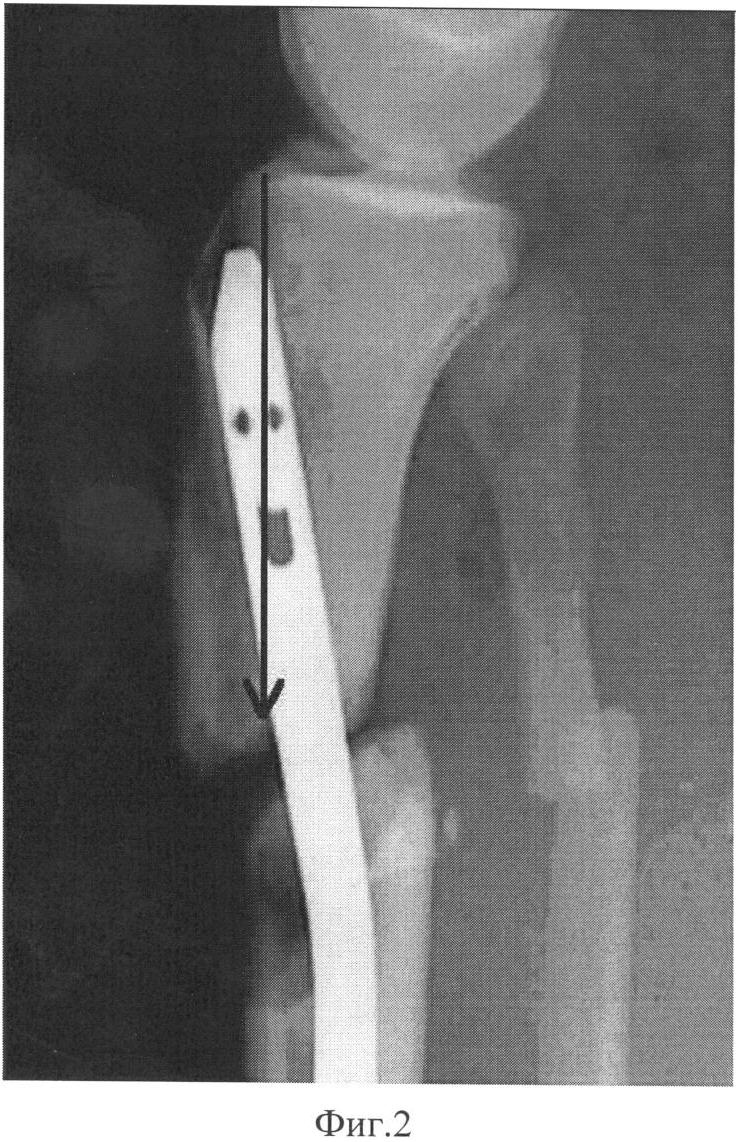

– при переломах проксимального отдела большеберцовой кости часто возникают проблемы вальгусной и антекурвационной деформации отломков (на Фиг.1 – типичная вальгусная деформация, на Фиг.2 – типичная антекурвационная деформация и смещение отломка кзади), что может потребовать операции при полуразогнутом положении колена для уменьшения тяги четырехглавой мышцы бедра, при этом требуется расширенный до 7-8 см доступ с артротомией, чтобы обеспечить прохождение стержня рядом с надколенником по межмыщелковой борозде бедренной кости при тенденции к прохождению интрамедуллярного гвоздя по направлению к задней стенке короткого проксимального фрагмента, а не по его продольной оси, необходимо использовать введение отклоняющего (Poller) винта, чтобы, отклонившись от него, гвоздь не был направлен к задней стенке фрагмента, что увеличивает время операции;

При переломах проксимального отдела большеберцовой кости дополнительно проводят спицу 7 во фронтальной плоскости за гребень большеберцовой кости кпереди от костномозгового канала максимально близко к нижнему концу проксимального отломка, спицу натягивают и закрепляют на консольных приставках на полукольце 1. При последующем сгибании коленного сустава для введения стержня эта спица препятствует появлению смещения под углом, открытым кзади, которое обусловлено тягой сухожилия четырехглавой мышцы бедра.

Для предотвращения типичного при введении гвоздя отклонения его кнаружи под рентгенологическим контролем проводят две отклоняющие спицы 8 спереди назад по середине поперечника большеберцовой кости. Первая проводится ближе к суставной поверхности, вторая – ближе к дистальному концу центрального отломка. Для предотвращения смещения под углом, открытым кзади, и смещения периферического отломка кзади по ширине проводится отклоняющая спица 9 во фронтальной плоскости по середине поперечника. Спицы проводятся до выхода из второй стенки костной трубки без выкола через мышцы и кожу на противоположной стороне. При введении интрамедуллярного гвоздя его направляют так, чтобы он прошел кнаружи от проксимальной и кнутри от дистальной передне-задних спиц и кпереди от фронтальной спицы, тем самым устраняется тенденция к вальгусу и антекурвации.